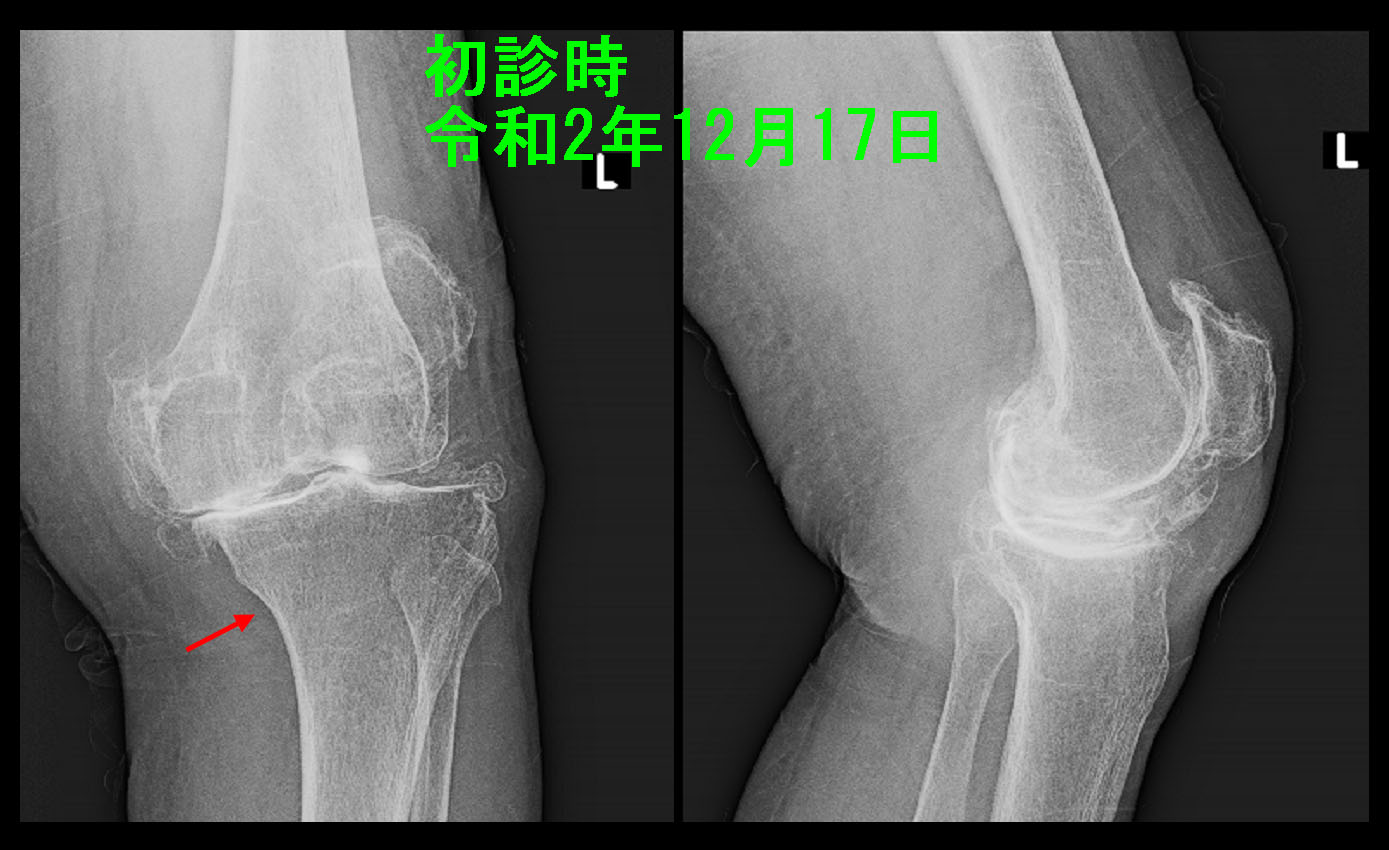

84才の独居の女性です。令和2年12月17日電車内での立ち上がり時に左膝痛発症し、そのままタクシーで当院を受診されました。

84才初診時.jpg

元々重度の変形性膝関節症があり、圧痛は左脛骨(下腿側の骨です)の赤矢印部分(内顆部)に確認されました。通常、変形性膝関節症の場合、圧痛は大腿骨と脛骨の隙間の部分にみられることが多いのですが、脛骨の内顆部の圧痛であったこと、痛みが発症すると直ぐにタクシー代を払って受診していることを考慮すると、初診時から骨の異常の可能性を考慮してMRI検査をするべきだったのかもしれません。しかし、この時は痛み止めを処方して経過観察としました。

しかし、5日後の12月22日に左膝の痛みは増悪して受診され、この段階でMRI検査を施行しました。